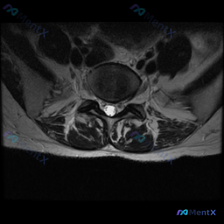

一张腰椎MRI轴位片说椎间盘病变?看完分析才知道很多人都理解错了

看到这张腰椎MRI-T2轴位影像,大家第一反应是什么?问题问的是椎间盘病变,整理一下分析思路和大家分享。

这是腰椎椎间盘层面(最可能为L4/5或L5/S1)的T2轴位扫描,我们先梳理所有客观发现:

- 椎间盘情况:中央区域信号较正常稍低,提示椎间盘脱水变性;但后缘形态完整,没有明显局限性突出/脱出,和硬膜囊前缘界限清晰,也没有看到明确的纤维环后缘高信号区(HIZ),不支持明显纤维环撕裂

- 椎管与神经:硬膜囊形态没有受压变形,马尾神经排列整齐,没有受压推移;双侧侧隐窝、椎间孔都没有明显狭窄,也没有占位挤压神经根

- 骨性结构与韧带:椎体后缘皮质连续,双侧关节突关节间隙清晰、关节面光整,没有明显骨质增生或肥大;黄韧带没有肥厚钙化,也没有向内压迫椎管

- 其他:没有椎管内占位,椎旁肌肉信号正常,没有术后改变

- 最明确的发现:椎间盘退行性变/脱水变性,T2信号减低就是髓核脱水、蛋白多糖减少的典型表现,这个是影像直接能看到的

- 其次考虑:生理性/轻度退变,因为没有形态改变和神经受压,大概率是和年龄相关的早期改变

- 需要保留不确定性:不能完全排除细微纤维环撕裂或者非常早期的非压迫性椎间盘突出,因为单张轴位片可能显示不全

整体来看,这个影像最确定的结论是:此层面仅见轻度椎间盘退行性变,没有发现有临床意义的椎间盘突出、椎管狭窄或者神经压迫。